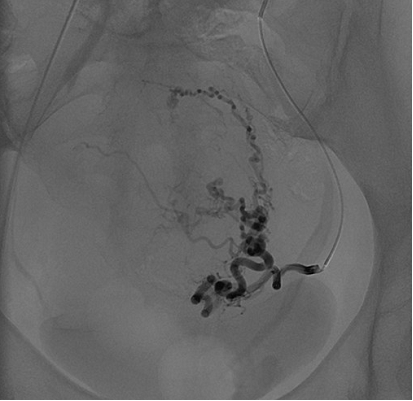

Bei der Uterus-Embolisation handelt es sich um ein Behandlungsverfahren, bei welchem die Gefäße, welche die Myome versorgen, unter röntgenologischer Kontrolle (teil)verschlossen werden.

Vor einer geplanten angiographischen Intervention wird zunächst zur besseren anatomischen Übersicht eine diagnostische Magnetresonanztomographie des kleinen Beckens inklusive einer Gefäßdarstellung durchgeführt. Im Rahmen des eigentlichen Eingriffes wird ein Katheter im zuführenden Gefäßsystem des Myoms platziert. Über diesen Katheter wird das zuführende Gefäßsystem embolisiert (verschlossen). Dies kann durch eine langsame Gabe von Kunststoff-Kügelchen oder auch Polyvinylalkohol (PVA) geschehen. Die kleinen Partikel fließen in die Endarterien des Myoms und verbleiben darin. Über mehrere Minuten werden die zuführenden Gefäße so blockiert. Dies führt zu einem Absterben des Gewebes im Myom und nachfolgend zu einer Verkleinerung und Symptomlinderung.